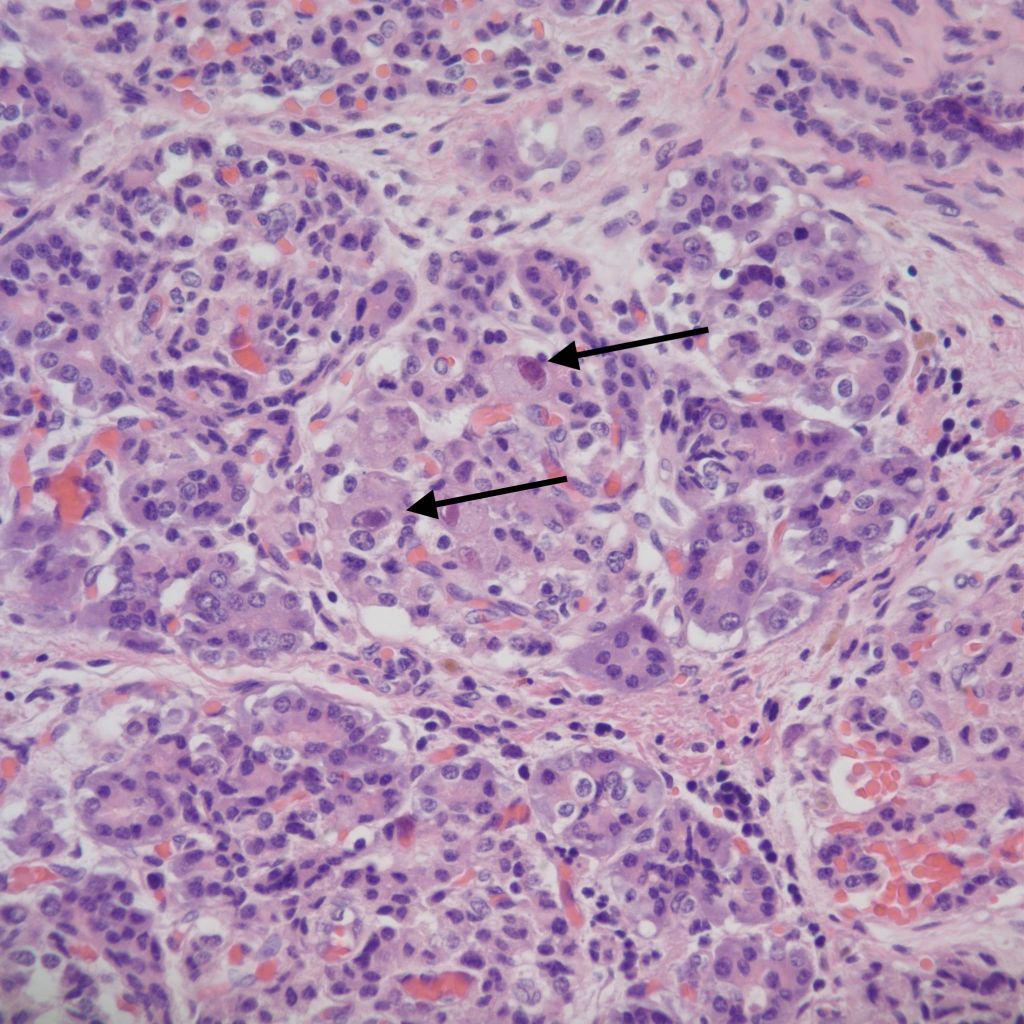

Necrobiosis of islets

The pancreas in shock shows “necrobiosis” of the islet cells, that is the nuclei become pyknotic and the cytoplasm eosinophilic (Fig 24). This lesion was identified as a lesion of cardiogenic shock in children dying of untreated hypoplastic left heart syndrome[21]. There is no report of an infant resuscitated from shock with a pancreatic polyendocrine deficiency.